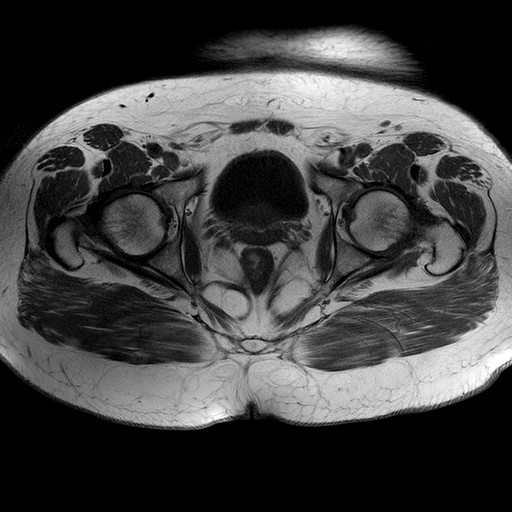

Esami: RMN BACINO

T1W_TSE

Evidenti e simmetriche alterazioni osteofitosiche in regione coxo femorale con riduzione delle rime articolari. Degenerazione completa del cercine glenoideo. Non attuali segni di versamento articolare. Non segni di edema osseo che escludono attuale algodistrofia od osteonecrosi. Lieve e simmetrica riduzione del trofismo della muscolatura glutea.